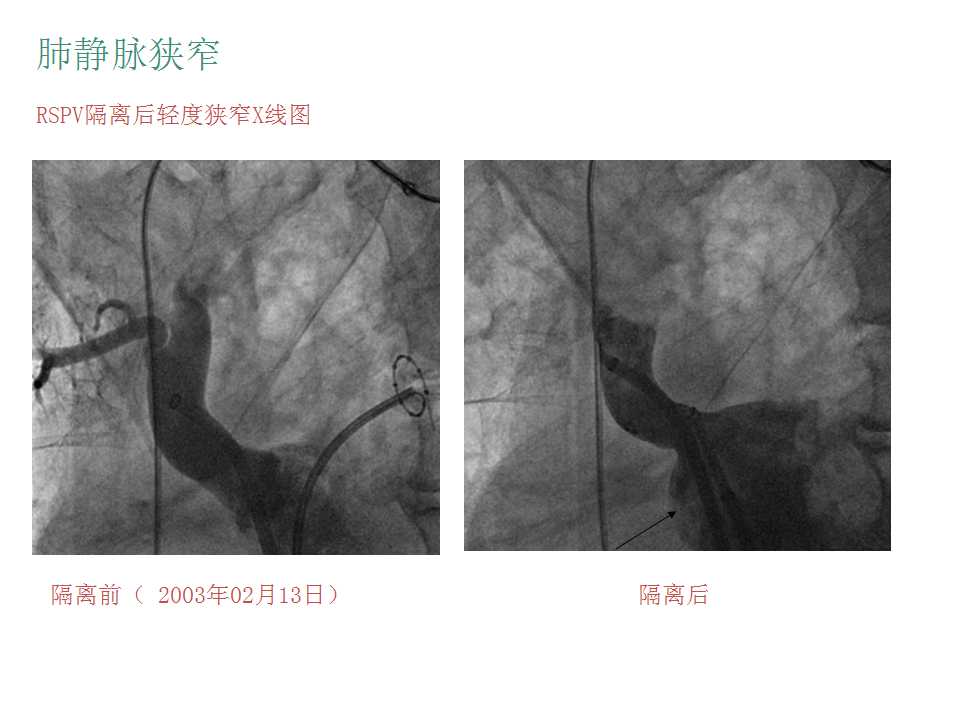

导管消融并发症的预防和处理